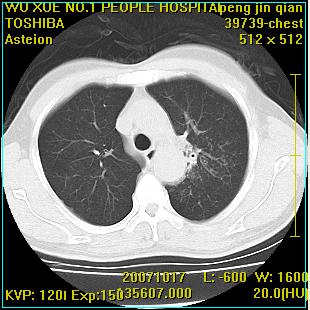

标题: CT10148:男,56岁,咳血。 [打印本页]

标题: CT10148:男,56岁,咳血。

左肺上叶尖后段较大团块影,边缘光滑,内见不规则裂隙样空洞,周围明显见细小结节及渗出,与肺门方向结构紊乱,另:左上叶尖段外侧 舌叶内侧 右上叶尖段及下叶背段均见片状致密影。考虑:继发性肺结核伴空洞形成!

右肺下叶背段/左上肺/左下肺结核伴空洞形成

结核 空洞伴两肺播散

支持结核可能,治疗后复查/活检,以除外结核肺癌同时存在